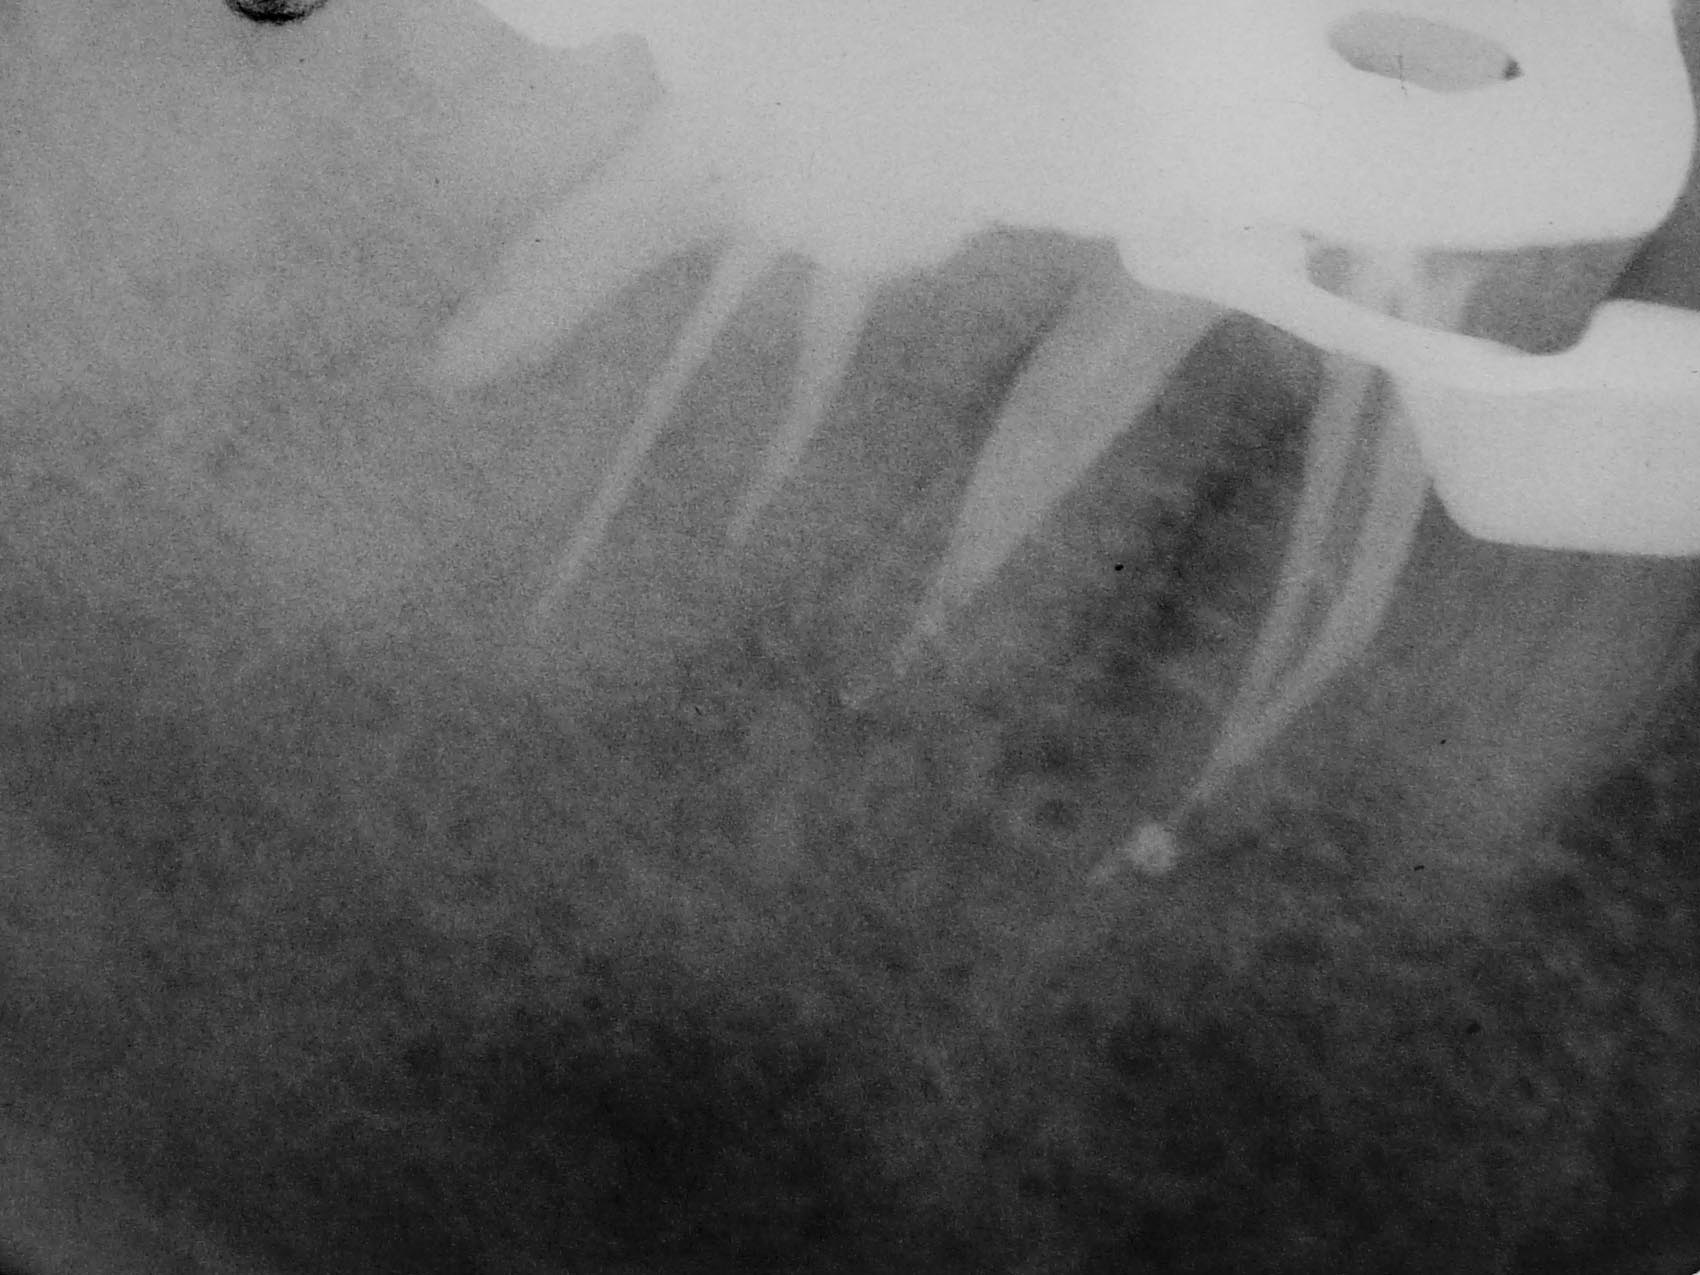

Rätselbild-5 Veröffentlicht 31. August 2009 am 1700 × 1275 in Shit happens: Das Rätselbild – Die Auflösung